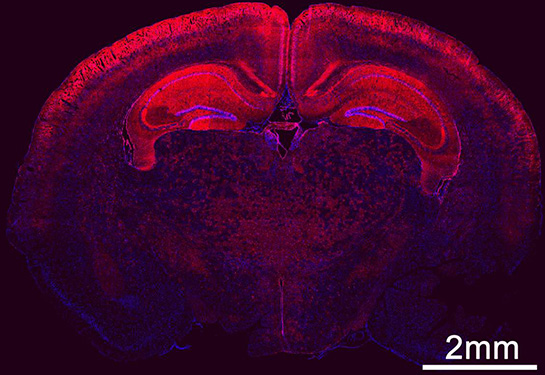

Read MoreA new biomedical tool successfully delivers genetic material to edit faulty genes in developing fetal brain cells. This might stop disease progression of genetic-based neurodevelopmental conditions and provide a cure by the time the baby is born.